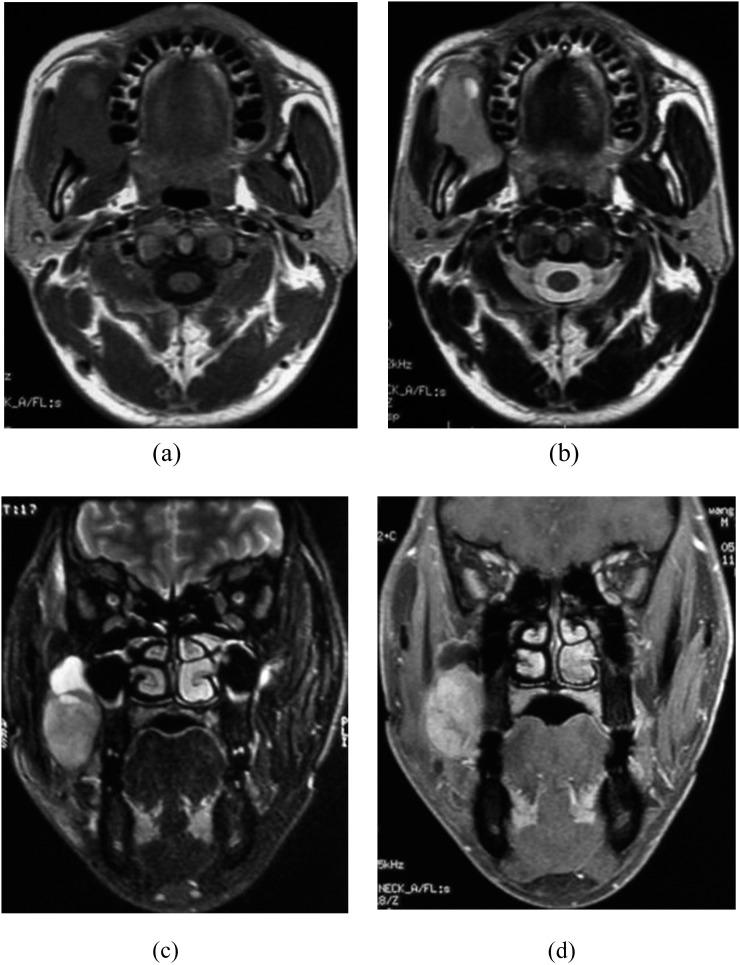

Four of all five cases were monophasic fibrous-type SS, and the other one was biphasic type that was the fourth documented SS located in the nasopharynx. The symptoms were varied. All the masses were well defined, mainly homogeneous and solid; three of them arose adjacent to the minor joint. The mass parenchyma showed isointense signal on T1 weighted imaging similar to that of the skeletal muscle and hyperintense signal on T2 weighted imaging with remarkable enhancement. Two cases were found with fibrous septum, one with haemorrhage and one with cystic degeneration. Epithelial membrane antigens (EMAs) were all positive. The positive rate of cytokeratin (CK), part pan-CK antibody (AE1/3) and vimentin (Vim) were 50%, 75%, 75%, respectively.

5例患者中4例为单相纤维型滑膜肉瘤,另1例为双相型,是第4例记录在案的位于鼻咽部的滑膜肉瘤。症状各不相同。所有肿块边界清晰,主要为均匀实性;其中3个起源于小关节附近。肿块实质在T1加权成像上呈等信号,类似于骨骼肌,在T2加权成像上呈高信号,并伴有明显强化。2例发现有纤维间隔,1例有出血,1例有囊性变。上皮膜抗原(EMA)均为阳性。细胞角蛋白(CK)、部分泛CK抗体(AE1/3)和波形蛋白(Vim)的阳性率分别为50%、75%、75%。